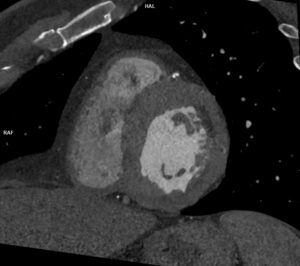

Figurile 4 si 5: reconstrucție multiplanară din examinarea recentă cu evidențierea subocluziei / ocluziei de la nivelul arterei descedente anterioare, in evolutie intre cele doua examinari

Discuţie caz nr 114: Examinarea cardioCT are indicație de clasa 1 la pacienții cu sindroame coronariene cronice; la acest pacient se poate observă evoluția în dinamică a unor plăci de la nivelul arterei descendente anterioare – indicația de repetare a investigației s-a datorat faptului că pacientul acuză dureri de tip anginos nou apărute la 5 luni după coronarografia cu implantare de stent pe arteră circumflexă.

DE LUAT ACASĂ!!! Examinarea cardioCT este indicată la pacienții cu sindroame coronariene cronice datorită valorii predictive negative mari, are tendința de a supraestima gradul de stenoză mai ales când este și calciu în placă și este urmată de coronarografia invazivă pentru diagnostic și, eventual, tratament în cazul în care se decelează stenoze severe (reducere de lumen mai mare de 70%).